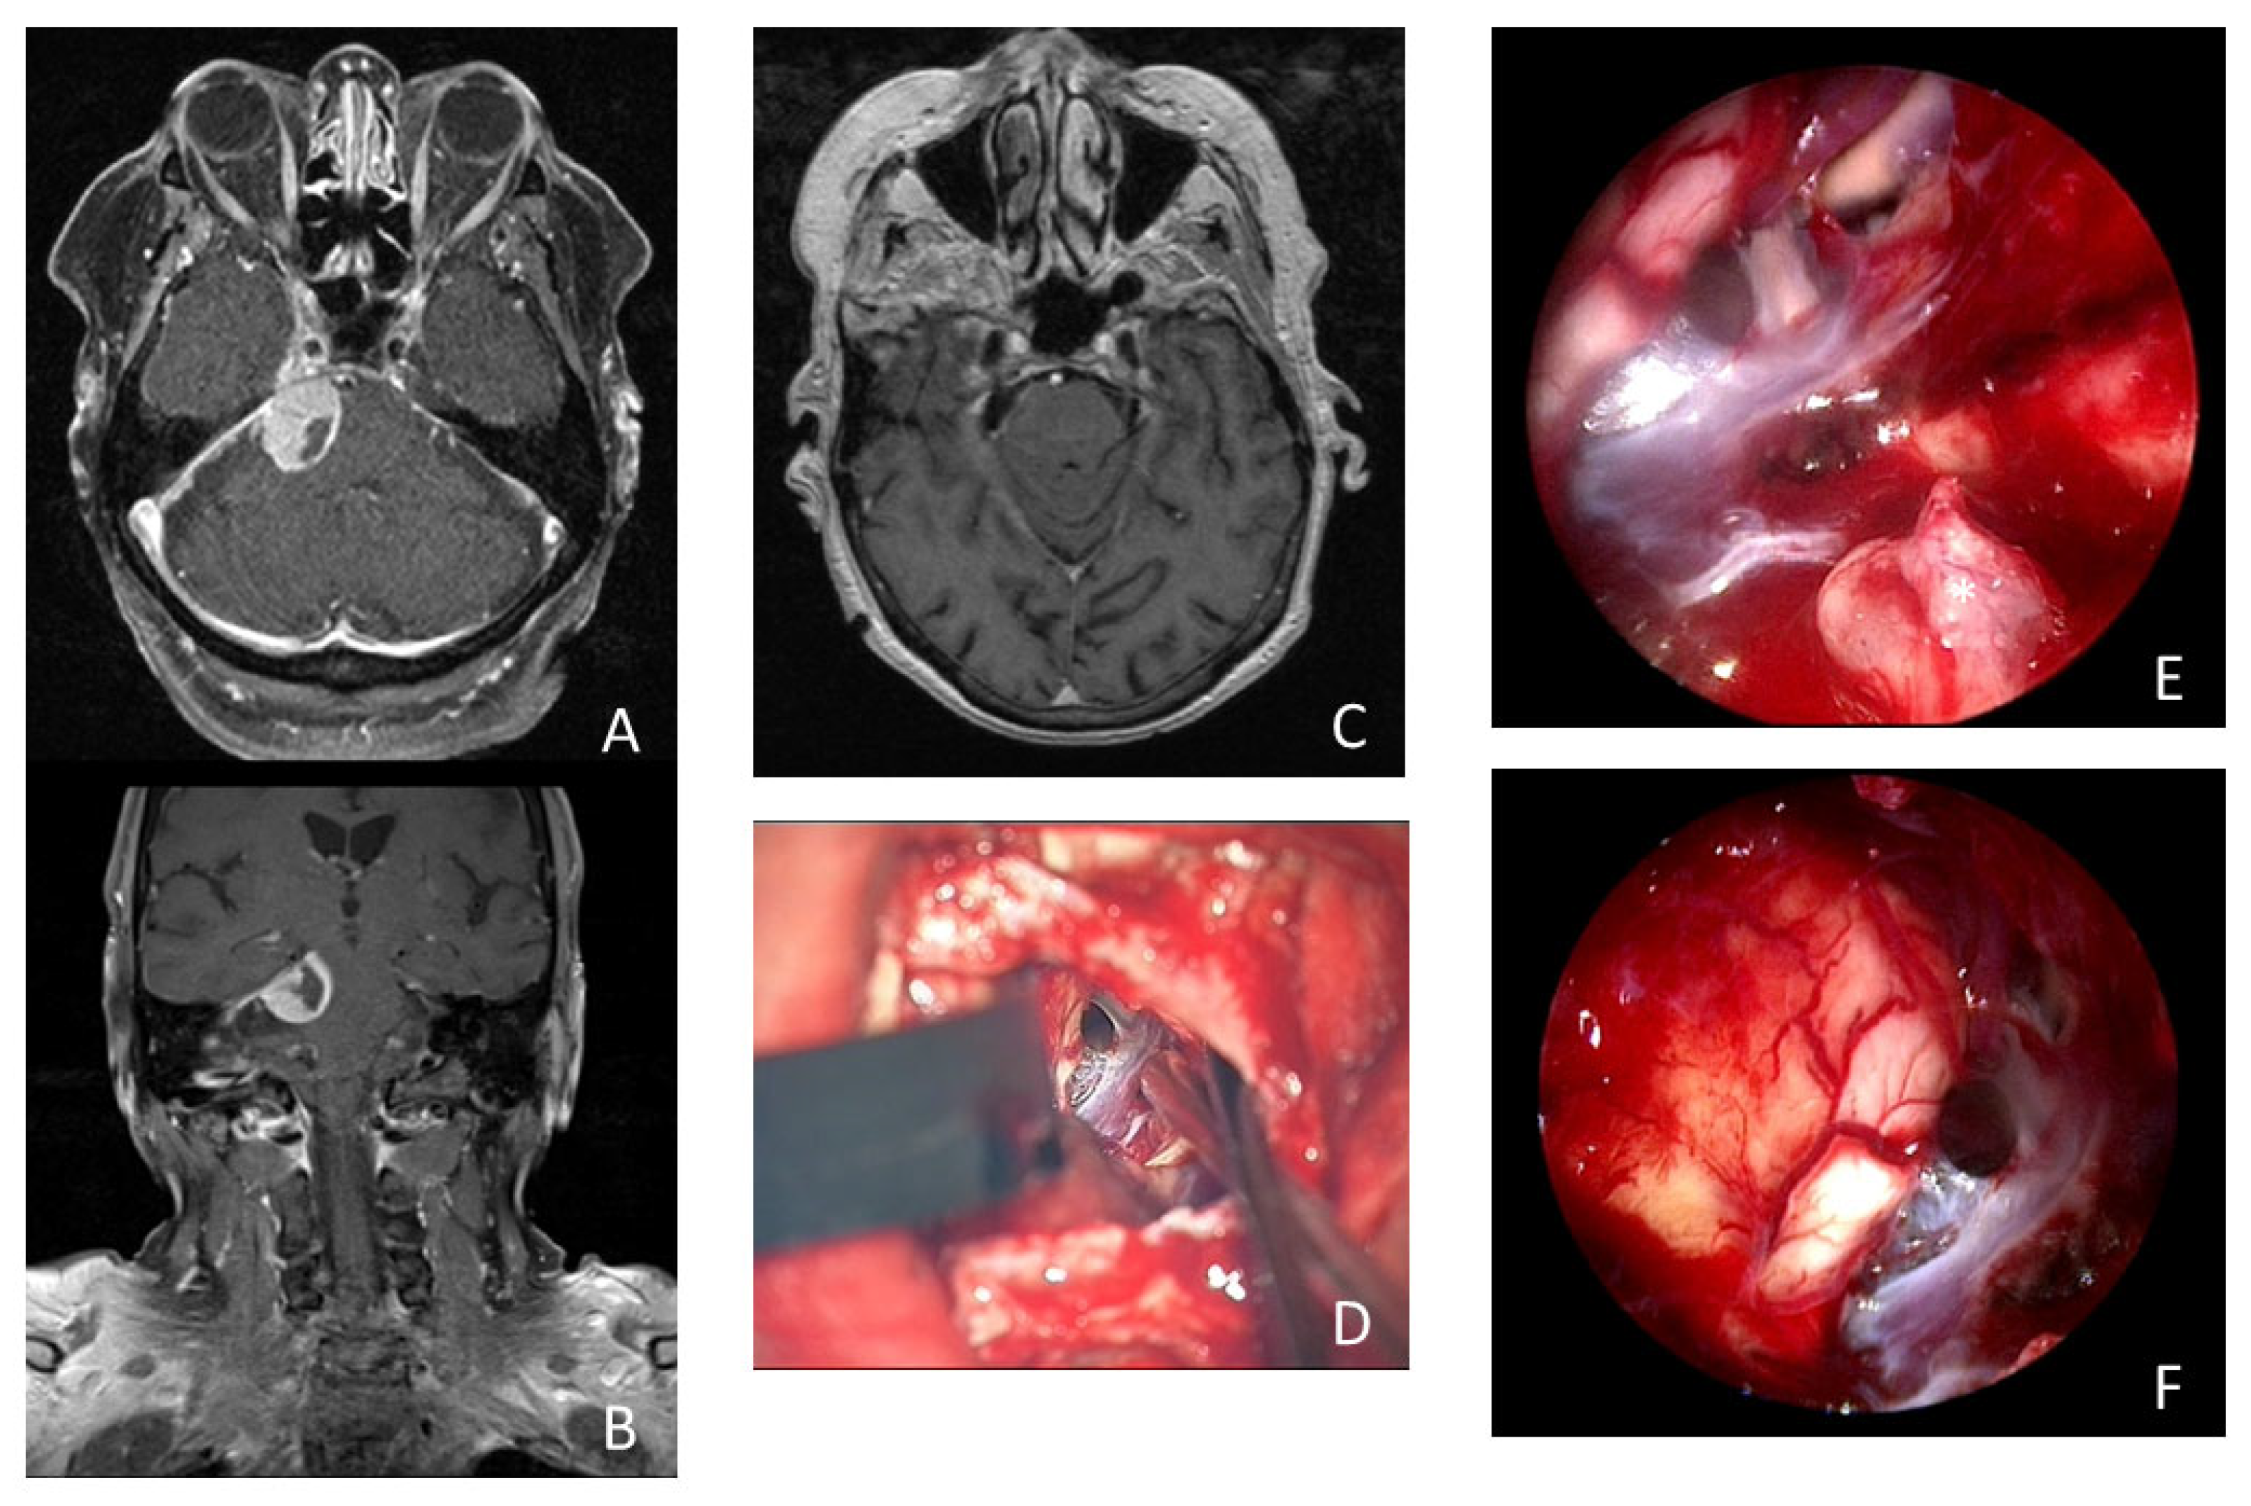

Illustrative case of a 74-year-old woman who presented with 3 months of persistent trigeminal neuralgia, diplopia, and headache. The MRI scan showed a tumorous lesion (15 × 19 × 16 mm) in the cerebellopontine angle with contact with the tentorium and Meckel’s cave in axial (A) and coronal (B) imaging. Postoperative MRI showed no remnant tumor tissue (C). (D) Microscopic view of the surgical field after resection of the meningioma. Intraoperative inspection with 30° endoscope revealed remnant tumor tissue (*) in the internal acoustic meatus (E). Intraoperative inspection with 30° endoscope into the prepontine space without remnant tumor tissue (F).

A 74-year-old woman presented with 3 months of persistent trigeminal neuralgia, diplopia, and headache. The MRI scan showed a tumorous lesion (15 × 19 × 16 mm) in the cerebellopontine angle with contact with the tentorium and Meckel’s cave. Gross total resection of the tumor was achieved using an endoscopic-assisted microsurgical retrosigmoidal approach in a semi-sitting positioning. Upon histopathologic examination, a meningotheliomatous meningioma WHO I was found. The patient’s complaints disappeared directly after surgery. She received MR imaging during follow up at 6, 12, and 24 months after surgery, showing no recurrence and no remnant tumor tissue (see Figure 3 and Supplementary Video S2).